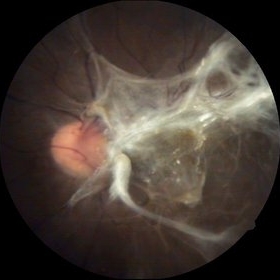

Rerinal Detachment with PVR

Sep 10 2014 by Mehul A Shah

A myopic male patient 35-years-old presented to outdoor and found to have retinal detachment with multiple fixed folds.

Photographer: Drashti Netralaya,Dahod

Imaging device: FF 450

Condition/keywords: proliferative vitreoretinopathy (PVR)